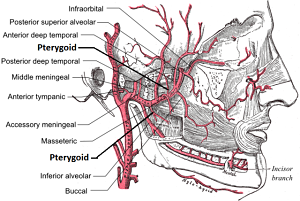

Desde el inicio de su recorrido en la articulación temporo-mandibular, la arteria maxilar entra en la fosa infratemporal del cráneo, un área está formada por los huesos esfenoides, maxilar, temporal y mandibular.

Luego continúa su trayecto hacia la fosa pterigopalatina, donde se relaciona con el músculo pterigoideo lateral, siguiendo un recorrido paralelo a él.

Dado que esta arteria aporta una cantidad considerable de ramas colaterales, se divide su recorrido en tres segmentos para simplificar su estudio anatómico.

Esta división se hace según la relación de la arteria con el músculo pterigoideo lateral. Así, se encuentran los siguientes segmentos:

– Segmento 1: también conocido como segmento óseo. Se ubica en el cuello de la mandíbula. En este pequeño trayecto la arteria da cinco ramas que se encargan de nutrir estructuras internas del cráneo.

– Segmento 2: denominado segmento muscular debido a que en esta parte sigue paralelamente al músculo pterigoideo lateral. Esta sección da cuatro ramos vasculares a estructuras bucales y también es la principal irrigación del músculo pterigoideo lateral.

– Segmento 3: llamado segmento pterigopalatino, es la porción que se encuentra anterior al músculo pterigoideo lateral y da ocho ramos vasculares que se encargan de irrigar el paladar, los músculos de la masticación y la región infraorbitaria.